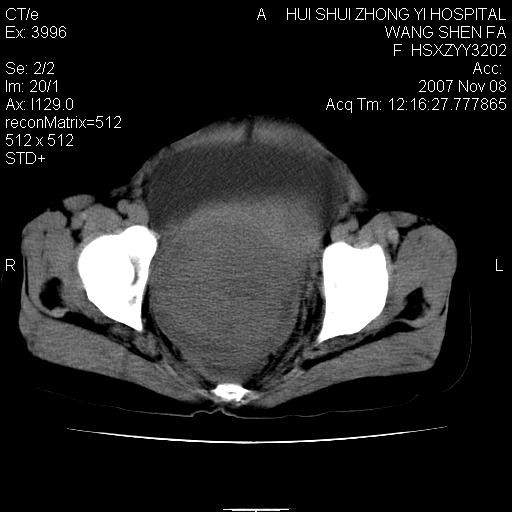

标题: CT10389:女,38岁,腹部巨大包块 [打印本页]

标题: CT10389:女,38岁,腹部巨大包块

腹部巨大包块半年,质硬,边界不清。

腹腔及盆腔内可见巨大软组织肿物影,内部密度欠均匀,边界尚清晰,周围组织受压移位明显,右侧输尿管受压明显,上端扩张肾盂轻度积水,病灶外形分叶明显,似多个肿物融合而成。考虑来源于间叶组织的恶性肿瘤可能性大

下腹部巨大软组织影,密度不均匀,并可见分隔,病灶边缘较清,肠管受压移位。子宫未显示。盆腔、双侧腹股沟未见明显肿大淋巴结。考虑:1.卵巢病变可能性大,囊腺癌>卵巢癌>囊腺瘤.2.多发性阔韧带子宫肌瘤待除外.

腹腔及盆腔内可见巨大软组织肿物影,内部密度欠均匀,边界尚清晰,周围组织受压移位明显,膀胱前上移位,右侧输尿管受压明显,上端扩张肾盂轻度积水。考虑:1卵巢病变可能性大,囊腺癌>卵巢癌>囊腺瘤.2 子宫病变,子宫肌瘤?